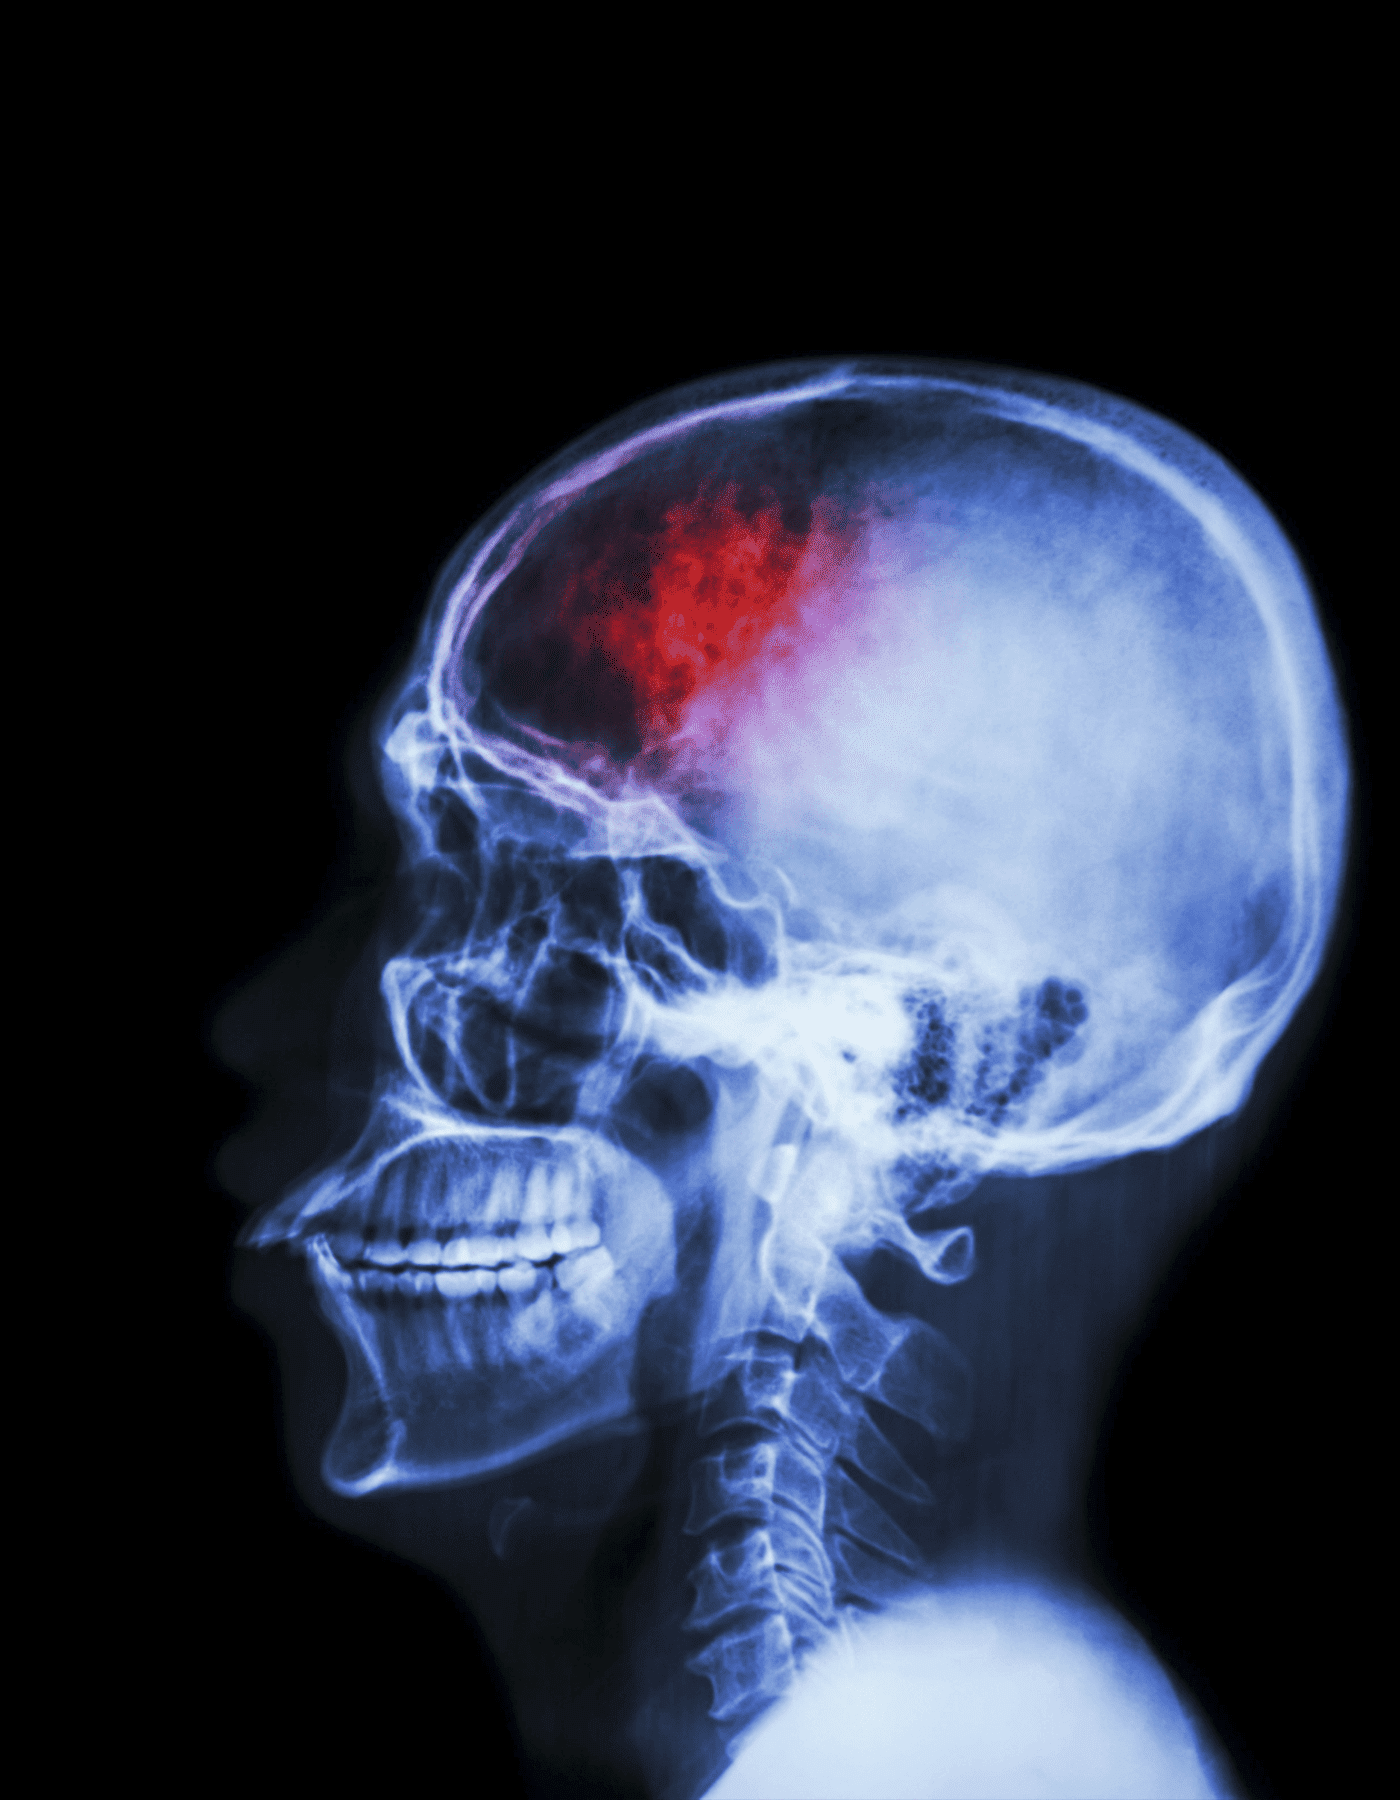

Los traumas de cráneo pueden resultar de accidentes, caídas o impactos deportivos, y varían desde leves hasta graves. Sus efectos pueden ser a corto plazo o tener consecuencias duraderas, por lo que es crucial un diagnóstico y tratamiento adecuados.

La evaluación de un trauma de cráneo incluye exámenes como tomografías y resonancias magnéticas. El Dr. Ventura Rendón utiliza estas técnicas para determinar la severidad de la lesión y la necesidad de intervención quirúrgica.

La cirugía puede ser necesaria para aliviar la presión en el cerebro, reparar fracturas craneales o tratar hematomas. Las técnicas quirúrgicas varían según el tipo y gravedad del trauma.